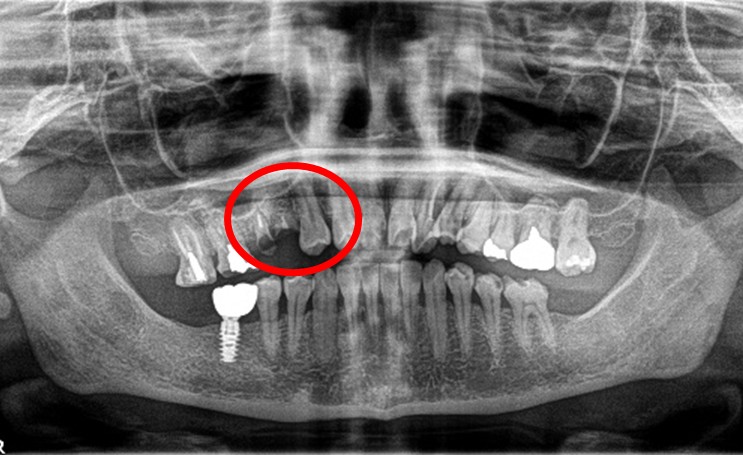

「右下の1番後ろの歯が浮いたような感じで、グラグラしていて噛むと痛みもあります。」とのこと。レントゲンで詳しく調べると、噛み合わせの問題と歯周病の進行が原因で、奥歯の周りの骨がなくなってしまっていました。この歯は残念ながら抜歯になることをYさんにお話しし、他の歯が多く残っているので、インプラント治療をおすすめしました。(インプラントは他の歯に負担をかけないので、残っている歯を守ることができます。)

この時はYさんはしばらく様子を見ることにされましたが、5月に再び来院され、「インプラントをお願いします」と決心してくださいました。合計2本のインプラントを入れ、Yさんは、「左右の歯で食べ物が噛めるようになり本当に良かったです。今後も歯を大切にしたいと思います。」と、とても嬉しそうにされていました。